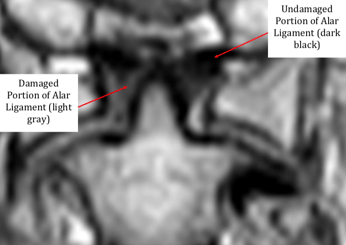

With this imaging sequence, ligaments can be seen in the cervical spine as dark black if they are healthy, and lighter gray if they have been damaged. These gray are- as are called high signal changes, and can be seen in the image shown above.

This is because after an injury, scar tissue that builds up in the damaged ligaments, creating a mottled gray appearance on the proton density sequence.